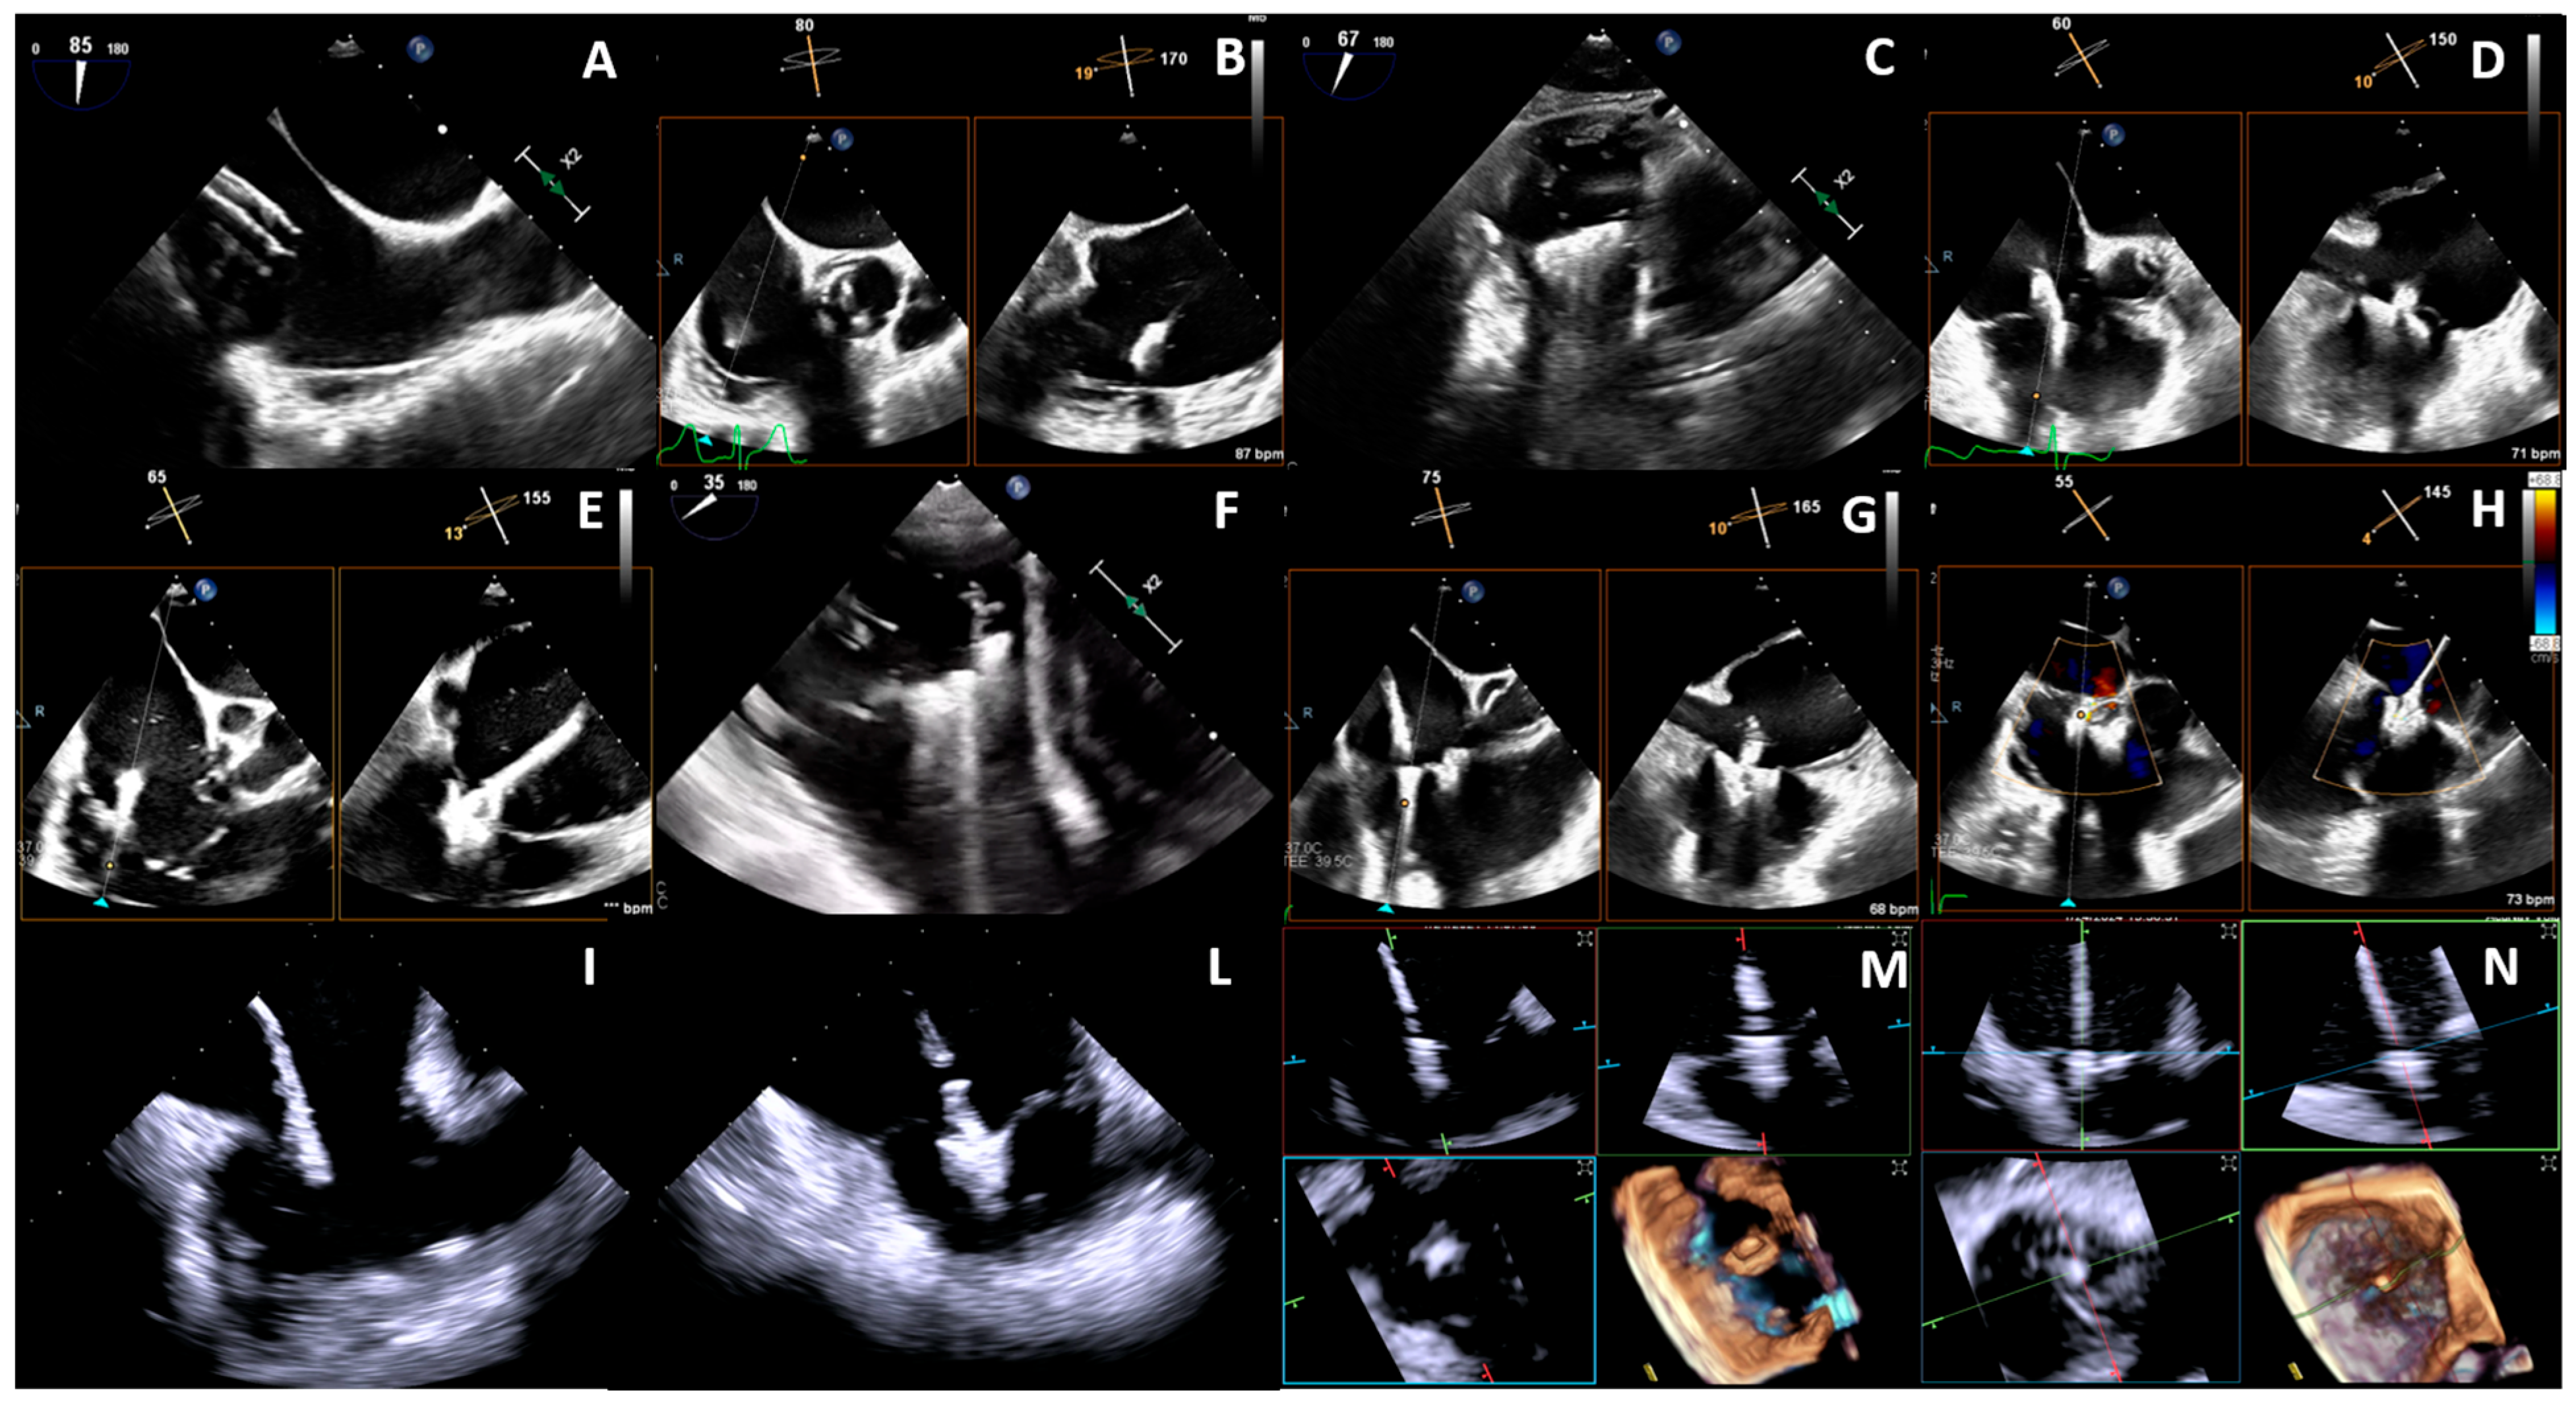

3.1. Transcatheter Edge-to-Edge Repair

3.2.2. The Cardiovalve System

- RA height: the height is calculated from the TV plane. The minimum cutoff is 60 mm to make the valve positioning feasible and to minimize the risk of complications during the advancement of the delivery system.

- RV length: the minimal distance between the apex of the RV and the tricuspid annular plane is 45 mm in diastole. Below the proposed cutoff, diving of the valve in the ventricle is not feasible.

- IVC offset and top distance: describes the distance and angular relationship between the entry point of the IVC into the RA and the TV annulus. This anatomical detail is crucial for the precise alignment of the delivery system with the TV annulus, for the trajectory and final positioning of the device. An offset less than 20 degree in diastole is usually favourable. The IVC top distance refers to the vertical distance from the superior aspect (or top) of the IVC to the TV annulus and it should be at least 50 mm to have a correct insertion depth and trajectory.

- Annulus diameters: minimal annulus diameter should be above 36 mm. Moreover, the shape of the annulus should not be too oval to avoid device mismatch. Cardiovalve has 3 different sizes that cover a broad range of diameters (45–55 mm).